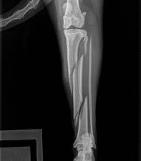

大腿骨骨幹の骨折

螺旋骨折のほか、破砕されて尖った長い骨片が生ずることが少なくない。骨片騎乗がおこる。

ふつう開放骨折になりませんが、筋、神経(会陰神経、脛骨神経)、大腿動・静脈に重度の損傷が生じます。

腫脹と著しい変形、激痛がある。骨片騎乗があれば捻髪音は明らかでない。膝蓋骨が転位しやすく、膝関節の機能異常が必発し(脛骨骨折の場合にはおこらない)、混跛を呈する。

患肢に負重せず、起立を欲しない。胸骨臥位では、肢が外側方へ屈折します。

子牛、子馬では髄内釘(特注)または骨プレートを用いて内固定をほどこし、これにThomas副子を併用します。ただし、感染の危険が小さくない。

ギプス包帯とThomas副子の併用が第一選択ではない。

成畜ではごくまれに、安静の保持で骨の癒合をうることがありますが、成豚(骨プレート使用)以外は、骨接合術が成功する可能性はほとんどありません。